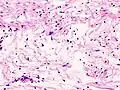

Micrograph of a schwannoma showing both a cellular Antoni A area (top) and a loose paucicellular Antoni B area (bottom). HE stain. -